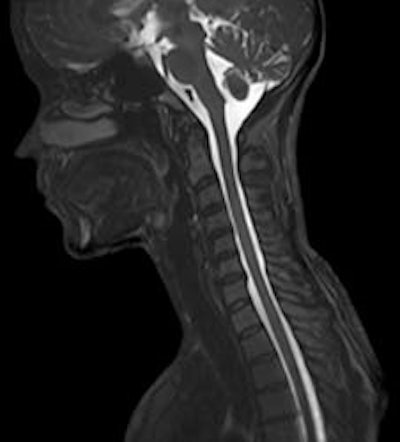

"It is a whole-body system fit for all clinical applications, but with an emphasis on broad clinical applications," Ohnesorge said. "Three-tesla MRI truly has proven its clinical differentiation, as in musculoskeletal, spine imaging, and neuroimaging, which in total is 70% to 80% of all MRI examinations. Some of the cutting-edge applications, such as functional MRI, are still subject to more clinical research."